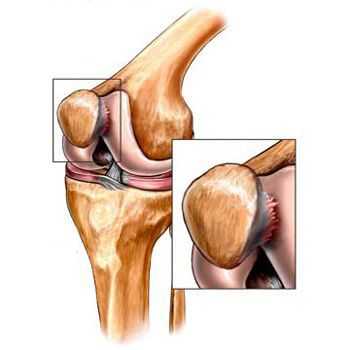

До середины восьмидесятых годов прошлого века не было унифицированного определения заболевания. Только к 1995 году комитетом по остеоартрозу Американского колледжа ревматологии заболевание было охарактеризовано как результат действия механического и биологического факторов, приводящих к дисбалансу между процессами деградации и синтеза внеклеточного матрикса суставного хряща. [11] [19] В итоге происходит его разволокнение и дегенерация, образуются трещины, остеосклероз и уплотнение кортикального слоя субхондральной кости, растут остеофиты и формируются субхондральные кисты. [12] [29]

При артрозе (остеоартрозе) кроме прогрессивного разрушения хряща, потери его эластичности и амортизирующих свойств, в процесс постепенно вовлекаются кости. [7] [29] Под нагрузкой возникают заострения по краям (экзостозы), которые по ошибке считают "отложениями солей" — при классическом артрозе никакого отложения солей не происходит. Прогрессируя, артроз продолжает «съедать» хрящ. Затем деформируется кость, там происходит образование кист, поражаются все структуры сустава, и нога искривляется. [11] [17]

Гонартроз, I стадия

Первая стадия заболевания характеризуется первичными изменениями в гиалиновом хряще. [12] [18] Костные структуры не затрагиваются. Во внутрикостных сосудах и капиллярах нарушается кровоснабжение. Становится сухой поверхность хряща, и он утрачивает свою гладкость. Если заболевание сопровождается постоянным напряженным синовитом, то развивается киста Бейкера (грыжевое выпячивание капсулы сустава подколенной области). [15] После значительной нагрузки на сустав возникают тупые боли. Возможна небольшая отечность, которая проходит после отдыха. Деформации нет.